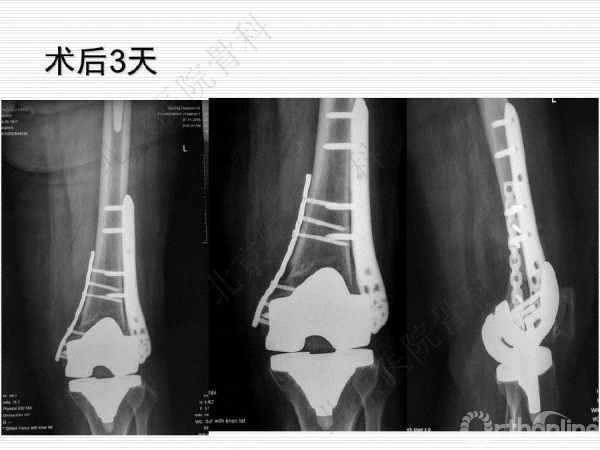

膝关节假体周围骨质疏松骨折1例

骨质疏松性骨折与创伤性骨折不同,是基于全身骨质疏松存在的一个局部骨组织病变,是骨强度下降的体现,也是骨质疏松症的最终结果。骨质疏松骨折是常见病、多发病,严重威胁中老年人身体健康,由此引起的骨质疏松性骨折,除了给患者本人造成极大的痛苦外,也给社会和家庭造成了沉重的经济和生活负担。来自北京医院骨科纪泉教授为我们带来一例经典的《膝关节假体周围骨质疏松骨折》病例,遂抗骨质疏松治疗预防再次骨折,任重而道远!